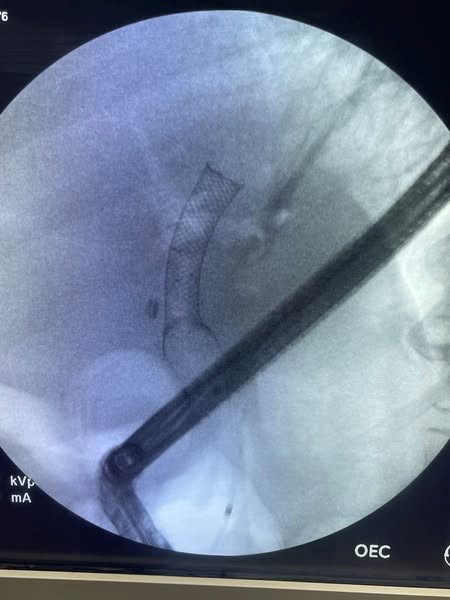

Extraction was done with dormia basket and washing then we use foreign body and fluoroscopy for removal of PCMS.

Insertion of double pigtail stent with good biliary flow.

Fig 1, Fig 2, Fig 3, Fig 4, Fig 5, Fig 6

Figure 3